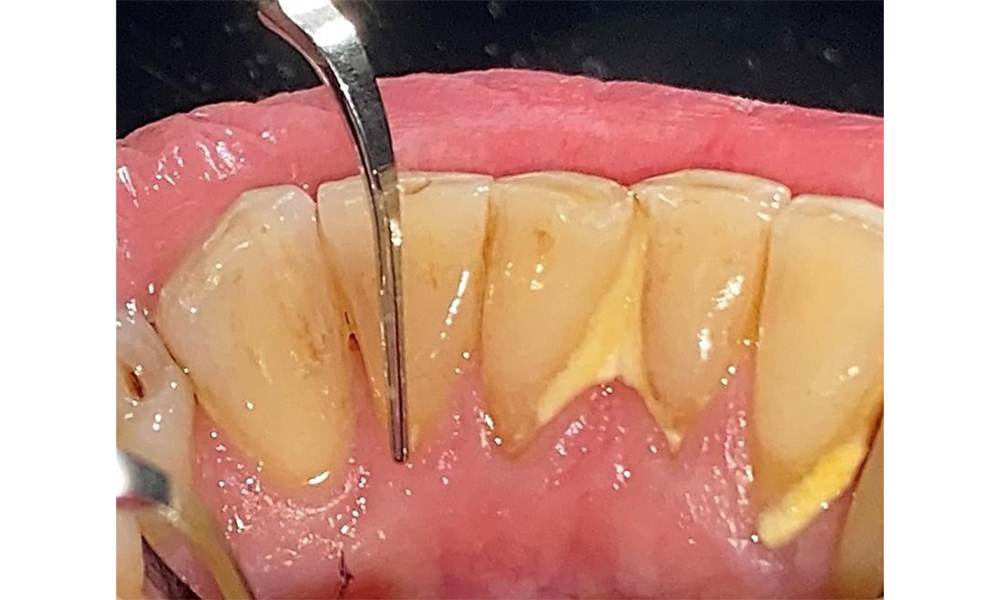

There are no limitations regarding the choice of instrumentation methods. Regular supragingival and subgingival instrumentation is essential to prevent disease progression due to the pre-existing periodontitis and high risk of recurrence. There are no limitations placed on the selection of instruments for mechanical biofilm removal from a general medical perspective, and removal should be performed as needed. Hard and mineralized plaque, such as calculus and concretions, should be removed using manual instruments or sonic/ultrasonic scalers (Fig. 9) (8, 9).

Use an ultrasonic tip to remove hard, mineralized plaque (Proxeo Ultra scaler with the Perio tip, W&H, shown here). © Dr R. Krapf

Fig. 9: Use an ultrasonic tip to remove hard, mineralized plaque (Proxeo Ultra scaler with the Perio tip, W&H, shown here). © Dr R. Krapf